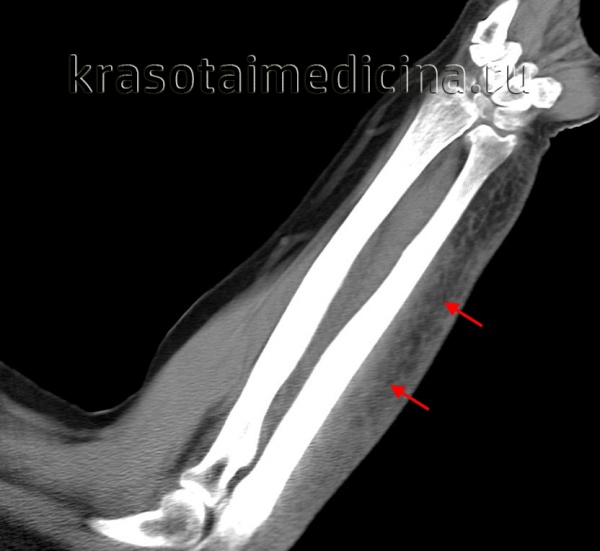

КТ предплечья. Геморрагическое пропитывание и отек мягких тканей предплечья со стороны лучевой кости (ушиб, подкожная гематома).